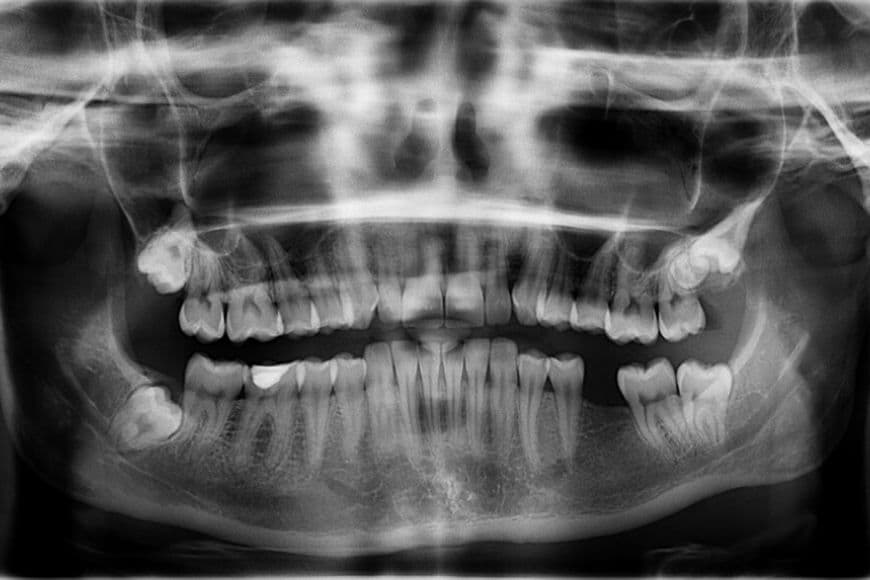

La panoramica è l’esame più comune e viene eseguito per conoscere il quadro completo della bocca. Permette di studiare le arcate dentarie, la posizione dei denti, le ossa mascellari e la mandibola. É utile per rivelare la presenza di carie, parodontiti, può evidenziare anche eventuali malformazioni dentarie o lesioni ossee, infiammazioni, granulomi, cisti o formazioni di altro genere. Si tratta di un esame molto semplice e rapido da eseguire che non richiede nessun genere di preparazione. Durante l’esecuzione l’operatore guida il paziente, chiedendogli di posizionare il mento su un apposito supporto e i denti anteriori su un altro, mentre le mani si tengono ad apposite maniglie. È importante che nel brevissimo tempo in cui sarà in corso l’esame, il paziente resti immobile per la buona riuscita dell’immagine. L’esito viene consegnato solitamente su un supporto digitale – cd o dvd – e può anche essere stampato.

L’esposizione alle radiazioni, con l’impiego delle tecnologie digitali, è davvero ridotta e – ad eccezione delle donne in gravidanza - questo permette che si possa eseguire un’ortopanoramica anche su soggetti più giovani come bambini e adolescenti.

Se l’ortopanoramica può offrire una visione di insieme della conformazione della bocca, in alcuni casi non fornisce particolari sufficienti e dettagli precisi.